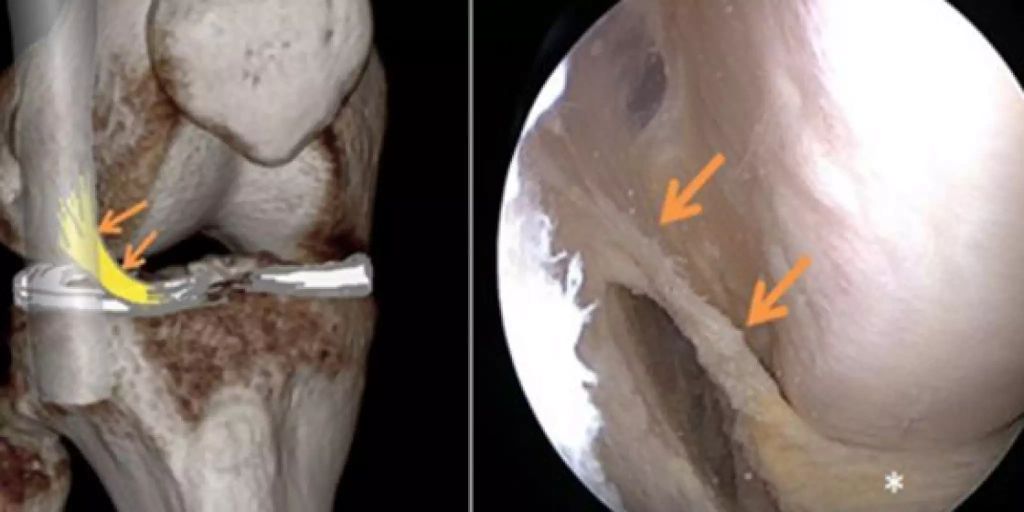

Sehnenentzündung am Knie Lumedis Ihre Sehnenspezialisten. Im Rahmen der arthroskopisch durchgeführten Operation wird die gerissene Sehne mit Hilfe einer Sehnennaht und oftmals zusätzlich einem Nahtanker fixiert. Ein Patella Sehnenriss (Riss der Patellarsehne) ist sehr selten